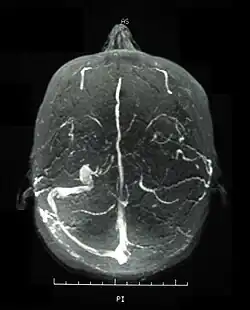

Magnetic resonance venogram demonstrating occlusion of the left sigmoid and transverse sinuses

According to the International Study Group guidelines, for a patient to be diagnosed with Behçet's disease,[24] the patient must have oral (aphthous) ulcers (any shape, size, or number at least three times in any twelve-month period) along with two of the following four hallmark symptoms.